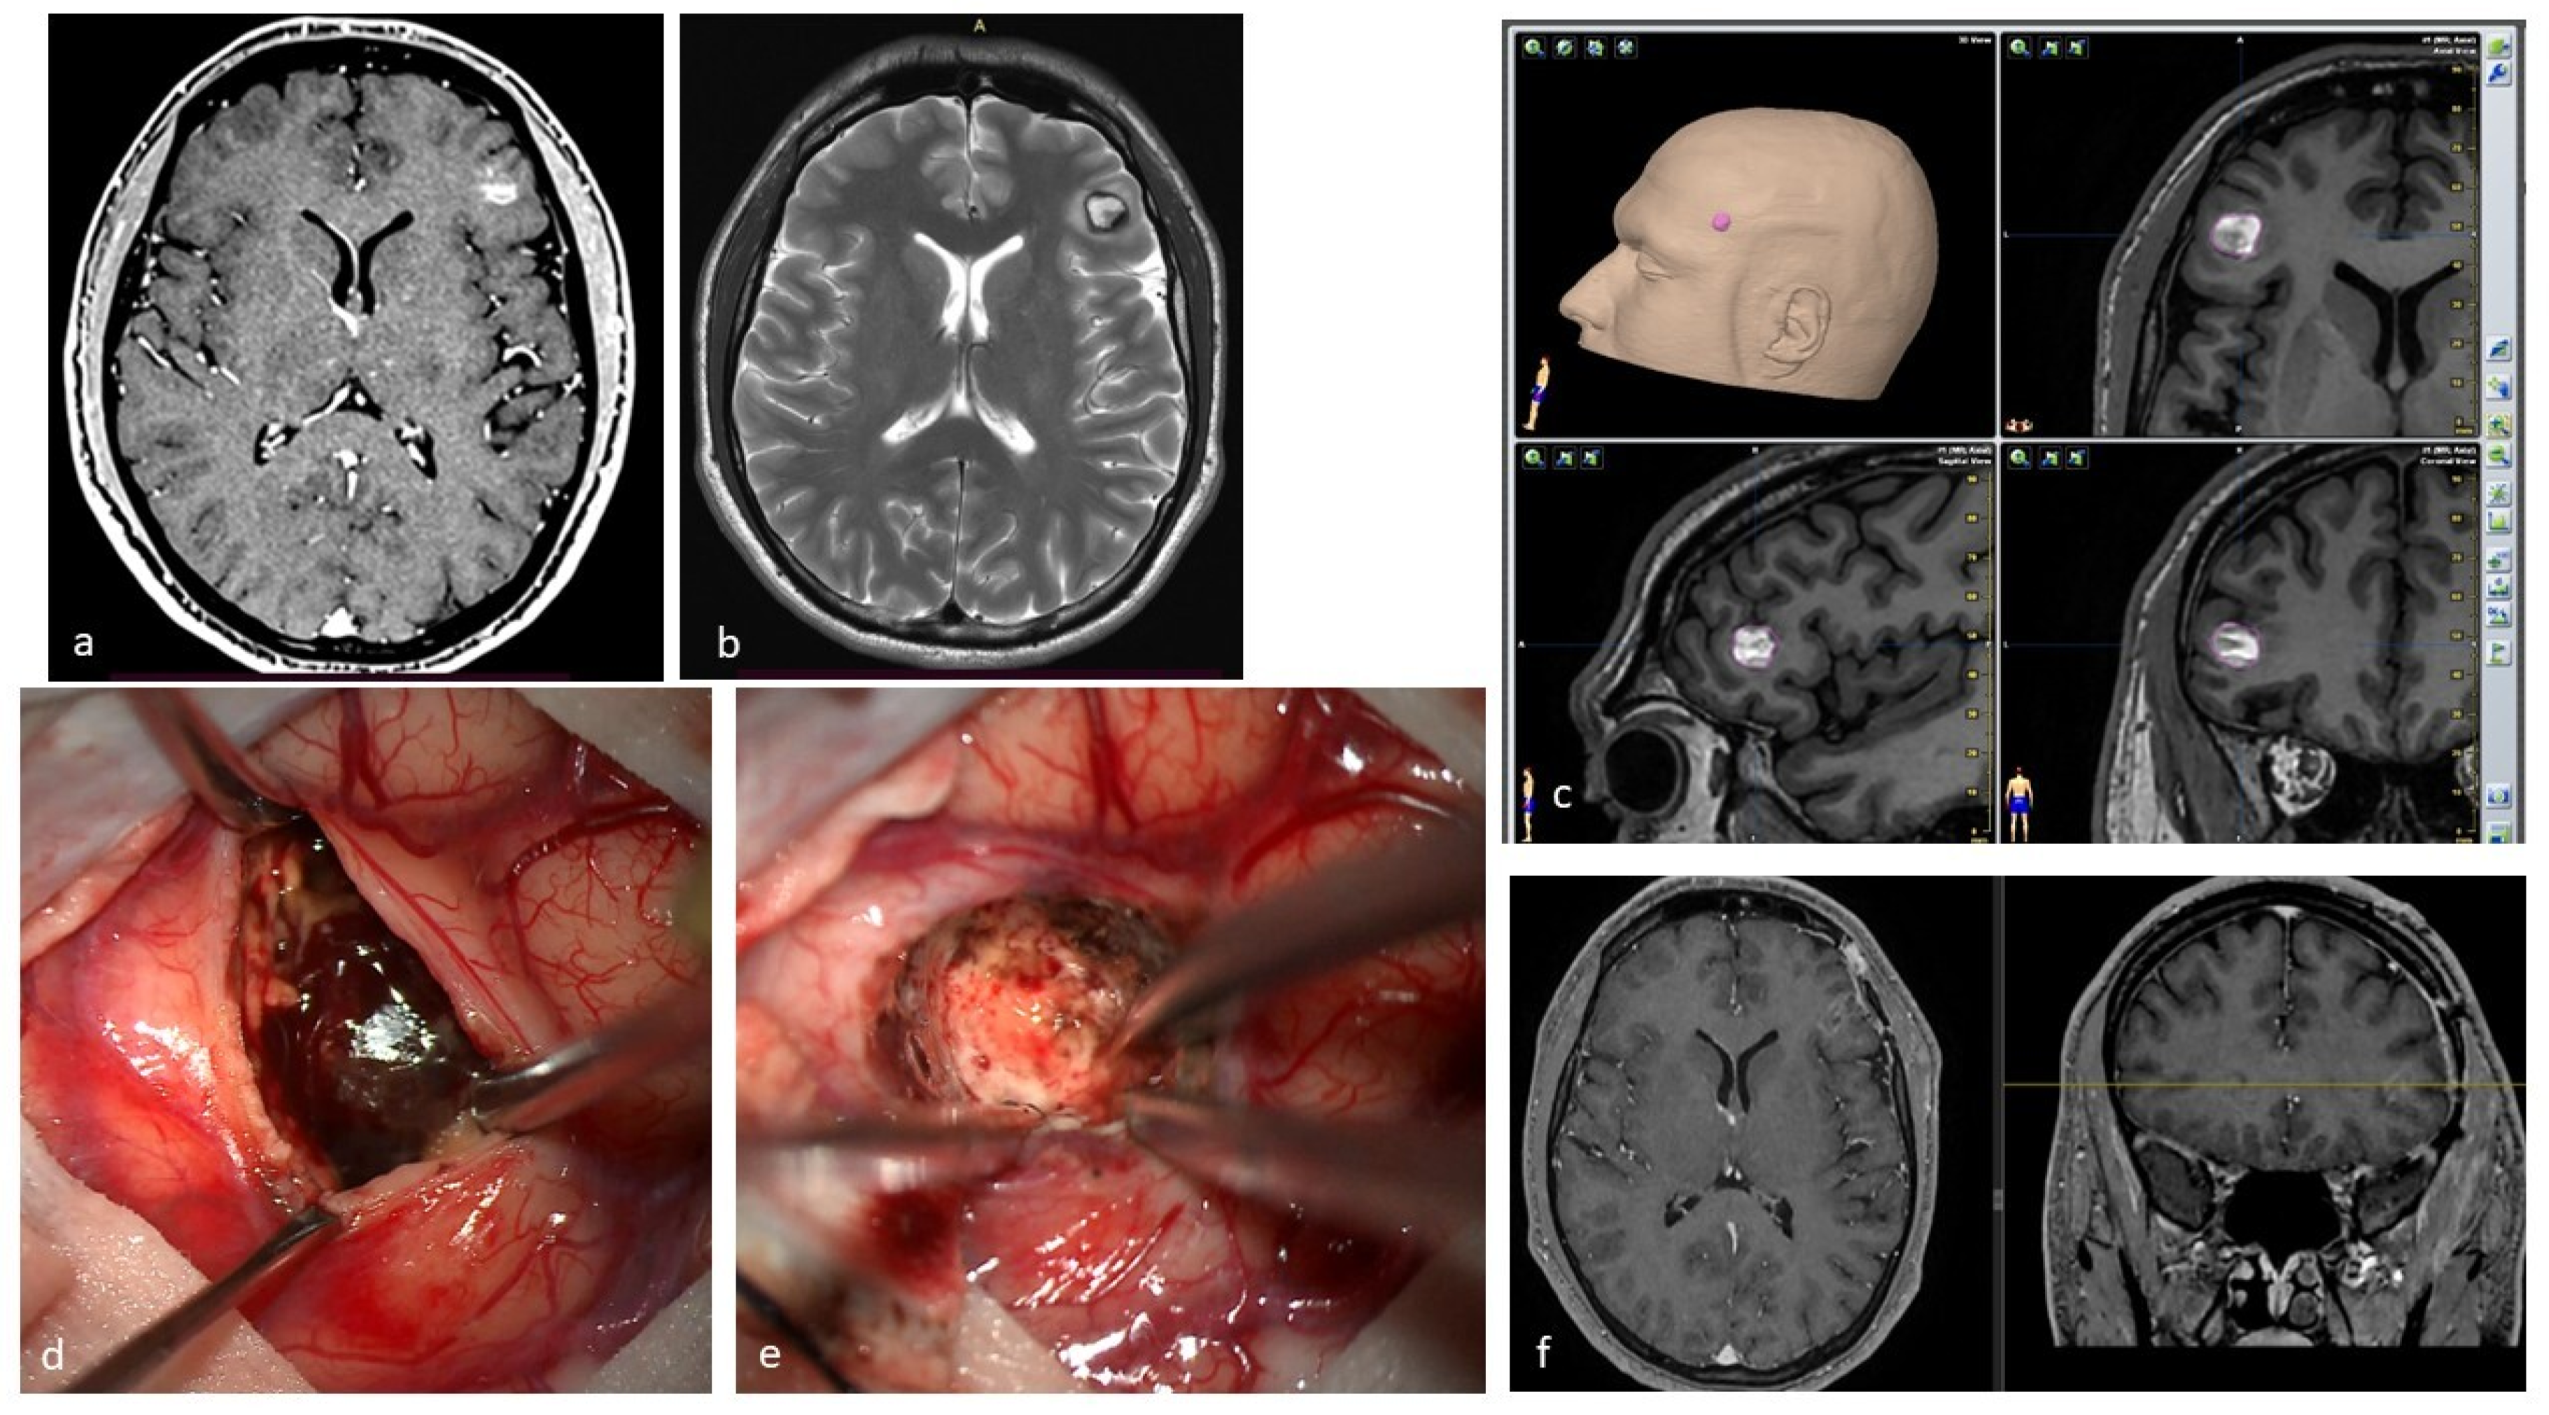

| Lesion Type | MRI Signal | Pathologic Features | Images |

|---|---|---|---|

| Type I | T1: hyperintense core T2: hyper- or hypointense core with surrounding hypointense rim | Subacute hemorrhage surrounded by a rim of hemosiderin-stained macrophages and gliotic brain | ![]() |

| Type II | T1: reticulated mixed signal core T2: reticulated mixed signal core with surrounding hypointense rim resulting in the “popcorn” appearance GE: low signal rim with blooming | Loculated area of hemorrhage and thrombosis of varying age, surrounded by gliotic, hemosiderin-stained brain; in large lesions, areas of calcification may be seen | ![]() |

| Type III | T1: iso- or hypointense T2: hypointense with a hypointense rim that magnifies the size of the lesion GE: hypointense with greater magnification than T2 | Chronic resolved hemorrhage, with hemosiderin staining within and around the lesion | ![]() |

| Type IV | T1: poorly seen or not visualized at all T2: poorly seen or not visualized at all GE: punctate hypointense lesions | Thought to be capillary telangiectasias | ![]() |